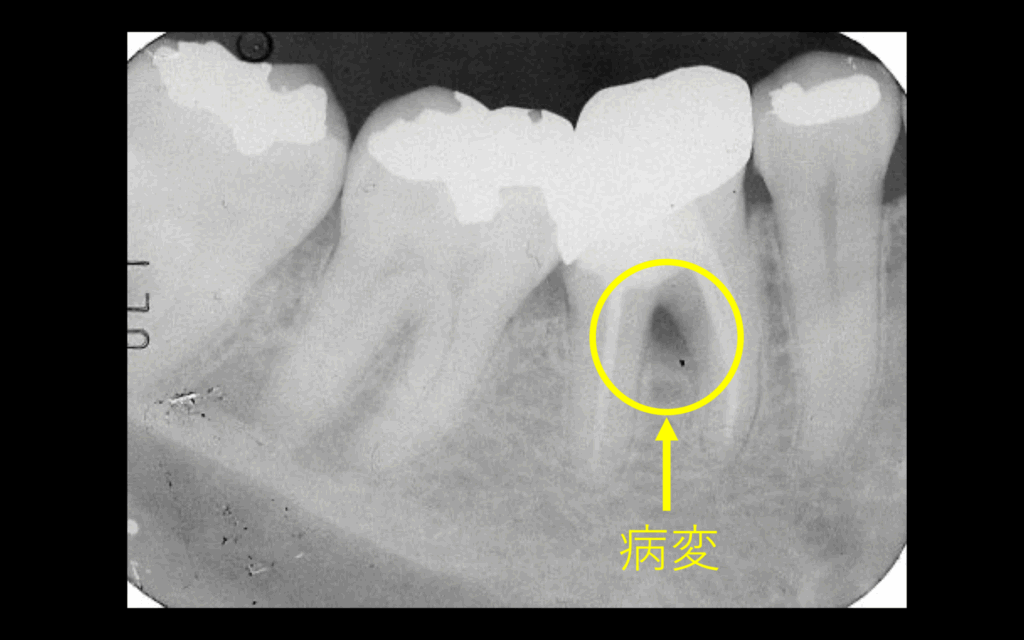

初診時。マイクロスコープで歯肉が腫れているの確認(左図)。レントゲン所見より、黒い部分が腫れている原因の病変である(右図)

術後はレントゲン撮影により経過観察。初診時のレントゲンにあった黄色の円で囲っている黒い部分の病変は、経過を追うにつれ、病変が小さくなり、骨が再生されてきているのが分かる。歯周外科(再生療法)などは行なっておりません。